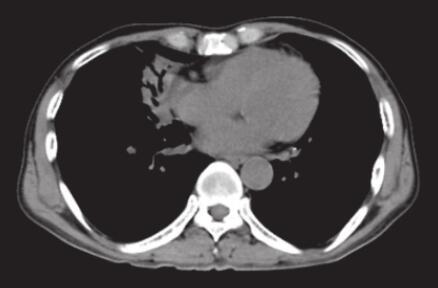

入院后给予亚胺培南西司他汀2.0g/d,静脉滴注治疗,患者体温降低,维持在37.5℃左右,咳嗽、咳痰等症状好转。血培养见放线菌。CT引导下经皮肺穿刺活检病理找到菌丝及孢子,拟诊真菌。2013年12月18日胸部CT示:右肺中叶大片高密度影,伴空气支气管征(图1)。

图1 2013年12月18日胸部CT

右肺中叶大片高密度影,伴空气支气管征

2. 主要表现为发热,咳嗽。查体右中下肺可闻及湿啰音,胸部CT右肺中叶大片高密度影,伴空气支气管征。

肺放线菌诊断的主要方法为支气管镜、经皮肺穿刺或外科手术切除活检病理诊断,有少数报道为痰涂片和胸腔积液中找到放线菌。肺放线菌病的影像学表现无特异性,可表现为实质性团块影、片状影、结节、支气管充气征、空洞、胸腔积液、纵隔淋巴结肿大及胸膜增厚,病变部位以左下叶居多,可能与吸入途径感染有关;右中叶次之。目前,罕见报道肺放线菌病PET表现,2012年欧洲胸部影像学年会报告显示病灶18F-FDG摄取值增高,SUV平均为(5.73±2.74),与肺癌难以鉴别。